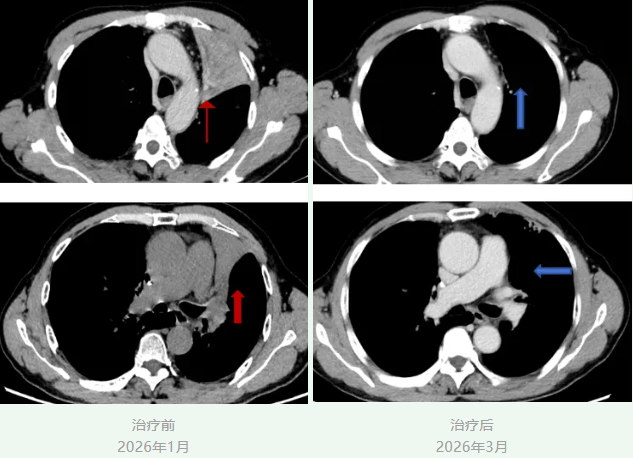

今年1月,患者出现活动后气促不适,来院复查胸部CT提示左上肺不张;支气管镜检查显示左肺上叶支气管增厚,活检病理提示肿瘤复发。患者为局部复发,相关检查未发现其他部位转移。鉴于左肺病灶已接受局部放疗,且放疗后1年内肿瘤复发,短期内无法再次行放疗。经我院胸部肿瘤内科与肿瘤与血管介入微创治疗中心医疗团队联合会诊评估后,为其制定了个体化治疗方案——实施经导管支气管动脉栓塞化疗术。

患者先后接受两次经导管支气管动脉栓塞化疗术。治疗后,患者活动后气促症状显著缓解;今年3月复查胸部CT显示,左上肺远端阻塞性炎症较前显著改善,病情得到控制。